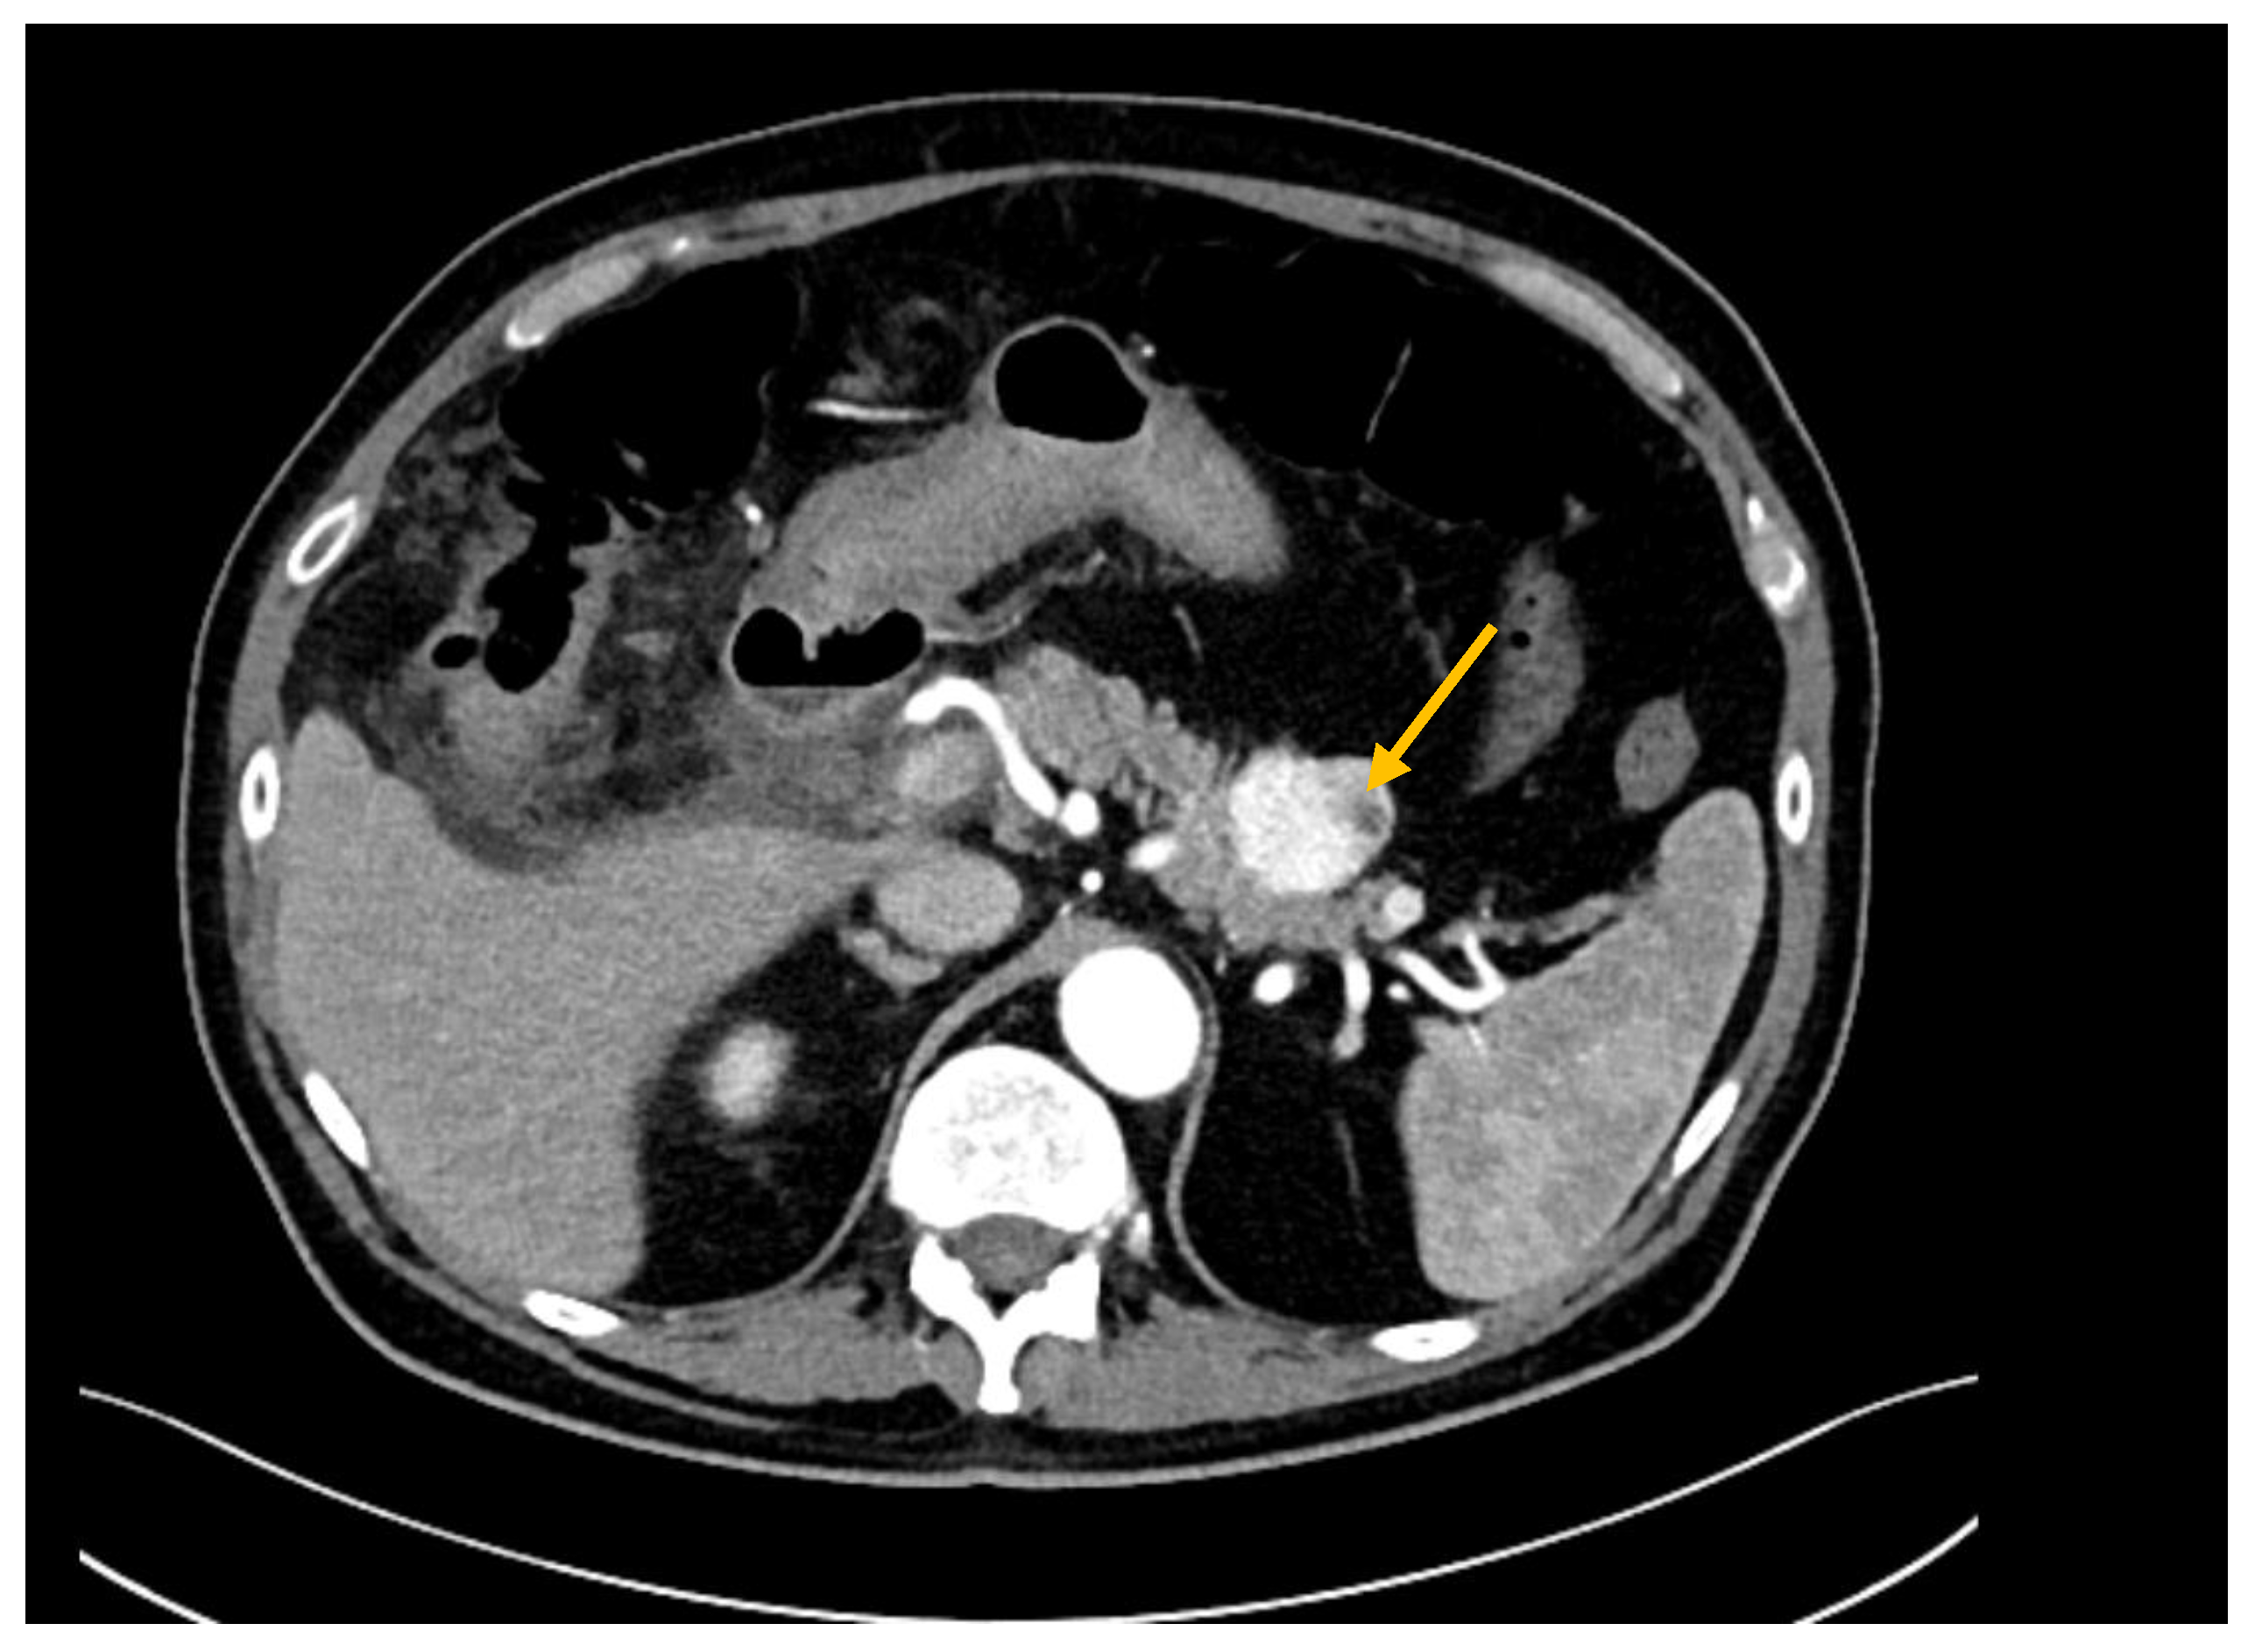

Figure 1.

CT scan showing a hypervascular lesion of the pancreatic tail (PM from RCC, yellow arrow).